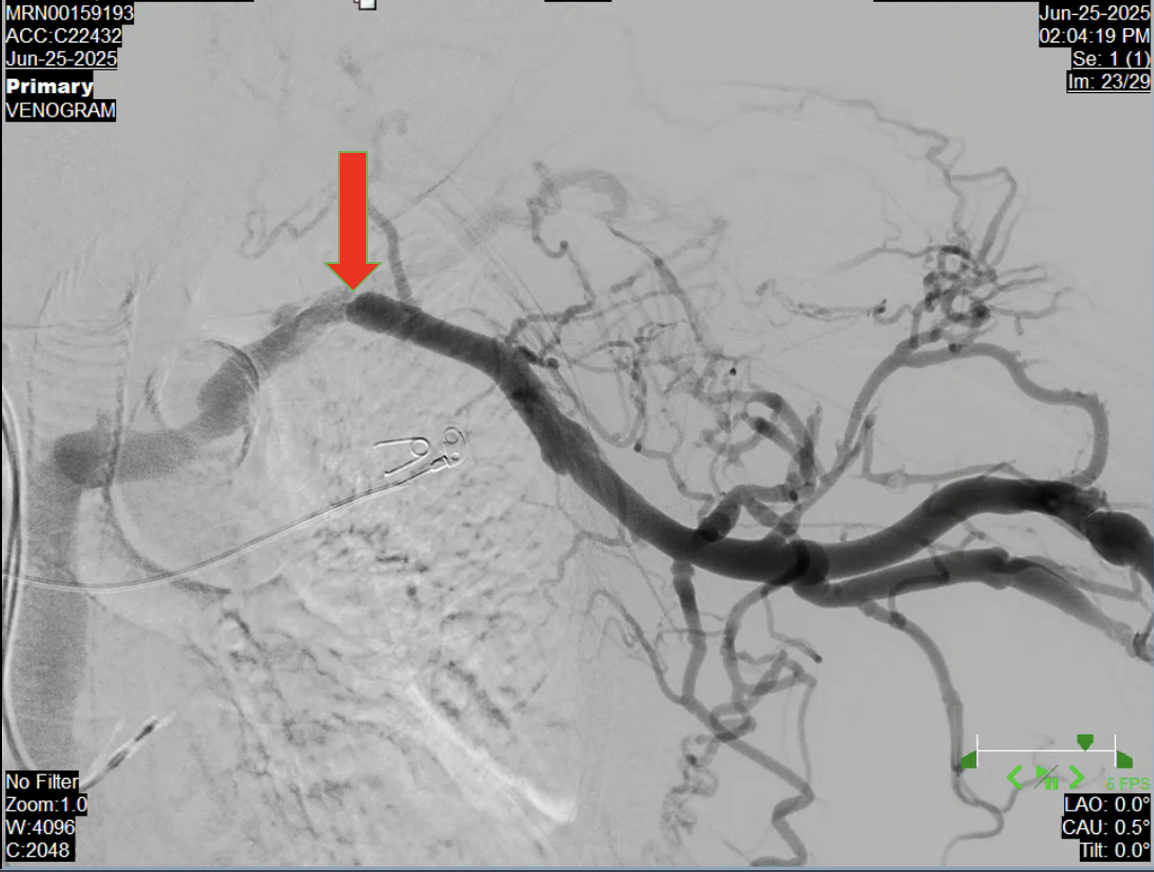

Digital subtraction venography revealed near total occlusion of the left subclavian vein at the level of the first rib wherein measurements taken on the lesion which was noted 90-95% stenosis. Multiple venous collateral formation with faint and sluggish antegrade collateral flow distal to the stenosis.

Left brachioaxillary graft was accessed using a Fr 4 hemostatic sheath. Venography done showing stenosis at the left subclavian vein at the level of the first rib. Mesurements taken with a degree of stenosis more than 95%. A balloon catheter was deployed using 10.0 x 40.0 mm Armada Abbott Catheter inflated at 10 atm for 30 seconds with gradual resolution of stenosis. Post venoplasty shots revealed normal contrast flow with disappearance of venous collaterals. No intraprocedural complications noted.